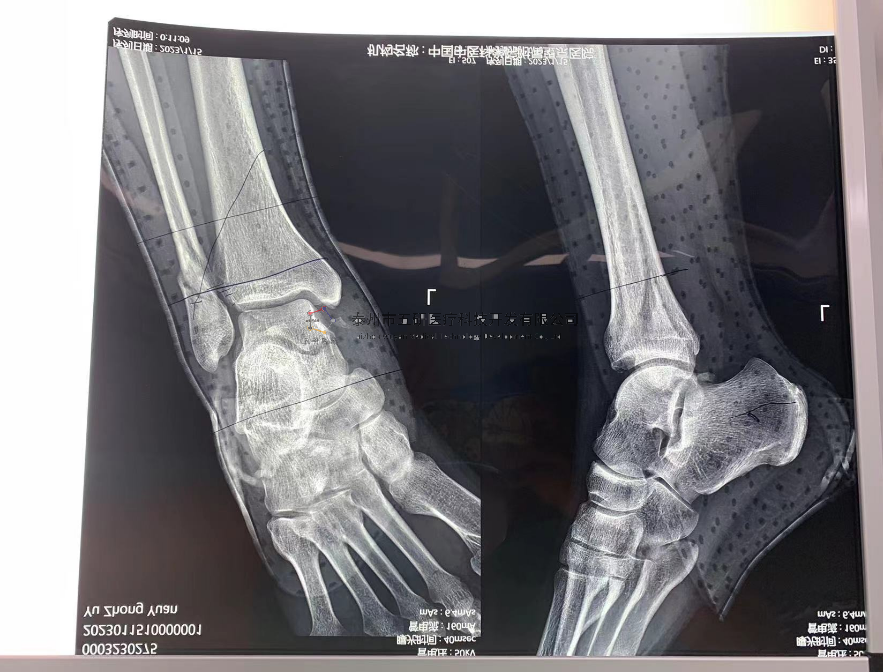

【治療后影像】

// 下肢骨折

【所屬科室】中國中醫(yī)科學(xué)院望京醫(yī)院創(chuàng)一科

【基本資料】患者,男,65歲

【患者情況】脛骨遠(yuǎn)端骨折伴腓骨骨折

【影像圖片—術(shù)前】

【影像圖片—術(shù)后】